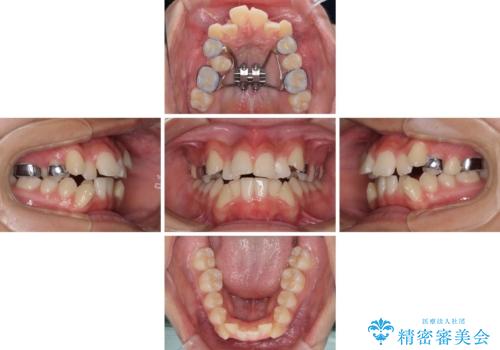

上顎骨幅が狭い 急速拡大装置を併用した抜歯矯正

- 歯列全体の叢生を気にして来院された患者様です。

検査を行った結果、上顎骨の横幅が相対的に狭いことが分かり、叢生が強いことから、急速拡大装置にて上顎骨を側方に拡大することで、叢生の解消と奥歯の咬み合わせ改善を図ることとしました。

一般的には上下左右の第一小臼歯4本を抜歯する必要がありますが、拡大量によっては非抜歯矯正の適用となる可能性があるため、まずは非抜歯矯正で治療を開始し、抜歯が必要と判断された時点で速やかに4本抜歯を行うこととしました。